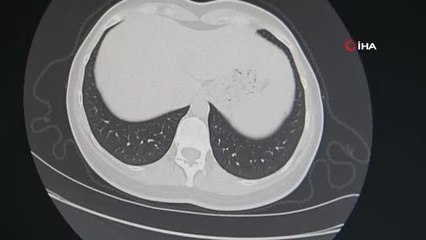

Mersin'in Erdemli ilçesindeki sigara bırakma polikliniklerine başvuranların yüzde 80'i, 25 günlük tedavi sonrası sigarayı bıraktı. Son bir yılda kent genelindeki polikliniklere 3 bin 339 kişi başvurdu. İl Sağlık Müdürlüğü sigara bırakma tedavilerinin ücretsiz olduğunu duyurdu. brPolikliniklere başvuranların yüzde 80'i sigarayı bıraktıbr Mersin'in Erdemli ilçesinde bulunan iki sigara bırakma polikliniğine başvuranların yüzde 80'i, 25 günlük ilaç kullanımın ardından sonuç alarak sigaraya alışkanlığından kurtuldubrMERSİN - Mersin'in Erdemli ilçesinde bulunan iki sigara bırakma polikliniğine başvuranların yüzde 80'i, 25 günlük ilaç kullanımın ardından sonuç alarak sigara alışkanlığından kurtuldu. Kent genelinde bulunan 9 polikliniğe son bir yılda 3 bin 339 kişinin başvurduğu öğrenildi. br Mersin merkez ve ilçelerinde 9 sigarayı bırakma polikliniği hizmet veriyor. Geçtiğimiz yıl kent genelindeki polikliniklerde 3 bin 339 kişinin sigarayı bırakmak için tedavi gördüğü belirtildi.br br hbrlr1.